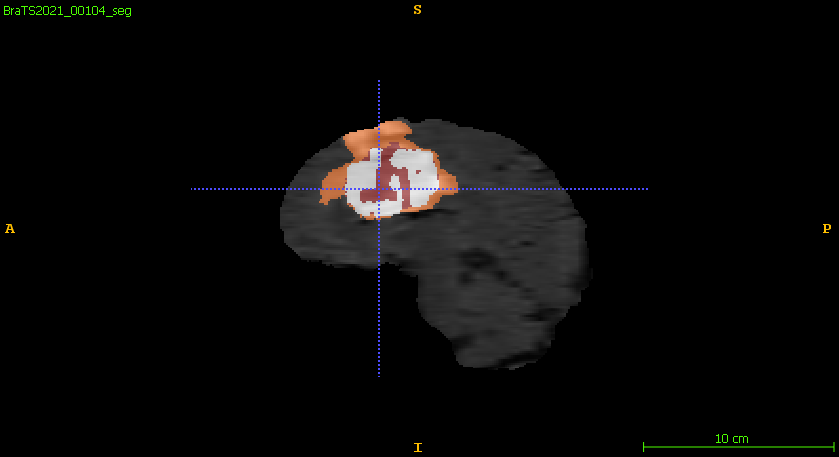

Furthermore, Figure 6 compares the ground truth on different planar views and the predicted segmentation labels corresponding to those views in the training set. The segmentation network demonstrates robust performance, accurately capturing the intricate details of tumor boundaries and structures across all planar views. The achieved DSC for the samples shown is 0.943 for ET, 0.957 for WT, and 0.949 for TC, reflecting the network’s high precision and reliability in segmenting different tumor regions. These results highlight the model’s effectiveness in generating segmentation outputs closely aligned with the ground truth.

Figure 6: Qualitative comparisons include (a–c) input FLAIR images with ground truth overlaid across axial, sagittal, and coronal views, (d–f) ground truth across the planar views, and (g–i) the corresponding predicted segmentation labels from the training set for each view.